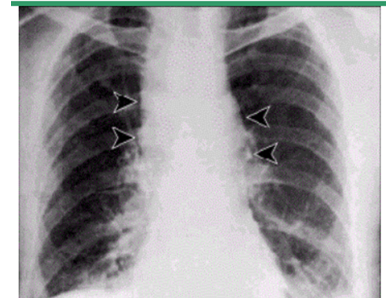

What is seen on CXR of the inhaled form of Anthrax?

(will be on exam)

Widened mediastinum